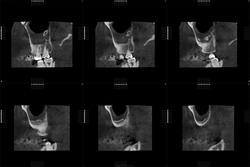

Здравствуйте, коллеги! Представляется КЛКТ ППН. Больной 31 г., направлен ЛОР-врачом на исследование ППН. В левой верхнечелюстной пазухе - костный фрагмент? Аномалия?

На серии изображений прослеживается в задних отделах левой (? ) верхнечелюстной пазухи септальная структура ( вариант строения ), острый синуит ( гайморит), фаза эксудации.

Да, это в левой пазухе.

Эта септальная структура, как мне видится, не связана со стенками пазухи...

Возможно, имеет место не костная, но хрящевая связь. Добавочная септа/перегородка - на мой взгляд, оптимальный вариант. Губчатая остеома выглядит здесь не то что редко, просто незнакомо. На зубик не совсем похоже. Вернее, совсем по-моему не похоже.)